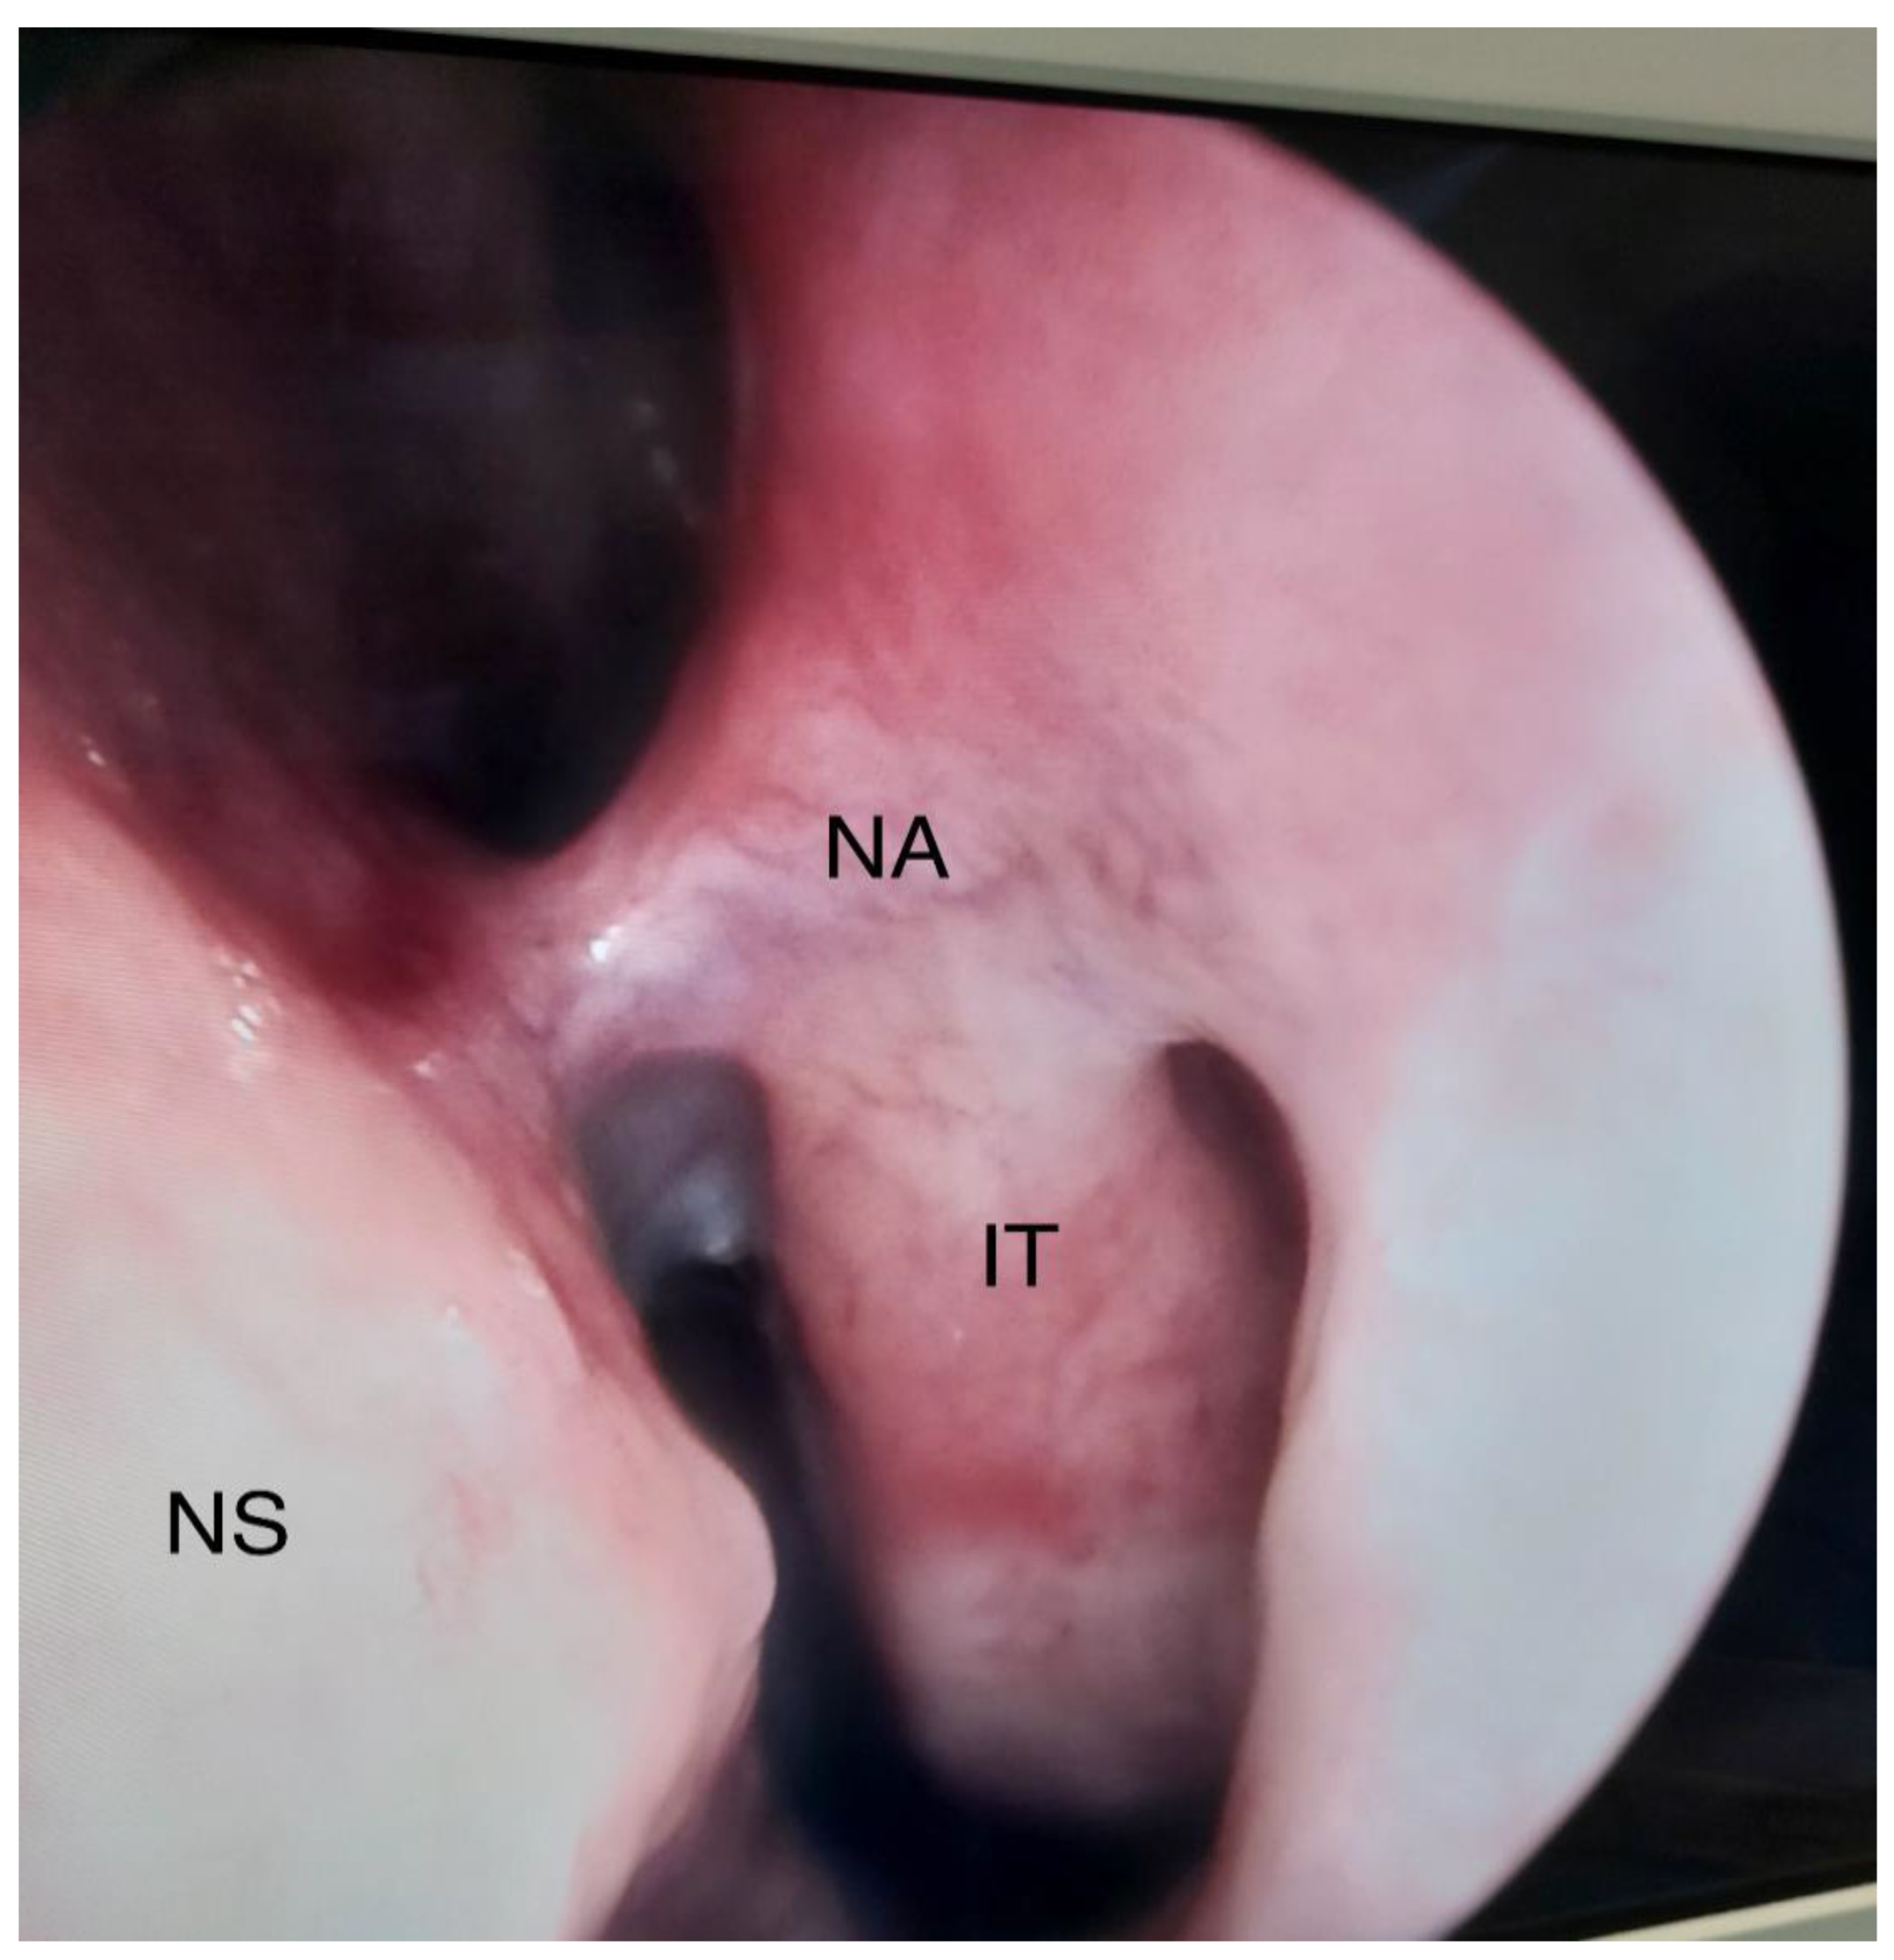

3.1.1. The Use of Nasal Splints in the Surgery of the Inferior Turbinates (Turbinoplasty)